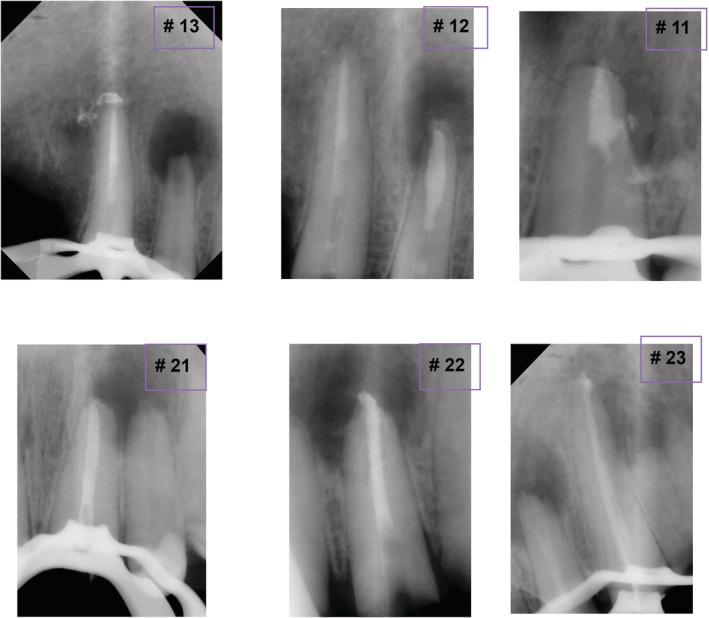

上颌切牙的外科根管治疗:病例报告

Surgical endodontic treatment of maxillary incisors: Case report.

This study aims to highlight the possibility of an effective endodontic surgical surgery when nonsurgical treatment of the right maxillary anterior teeth has failed. One year after the apicoectomy, the periapical lesion has completely healed, new bone has formed, and the patient is symptom-free.

摘要